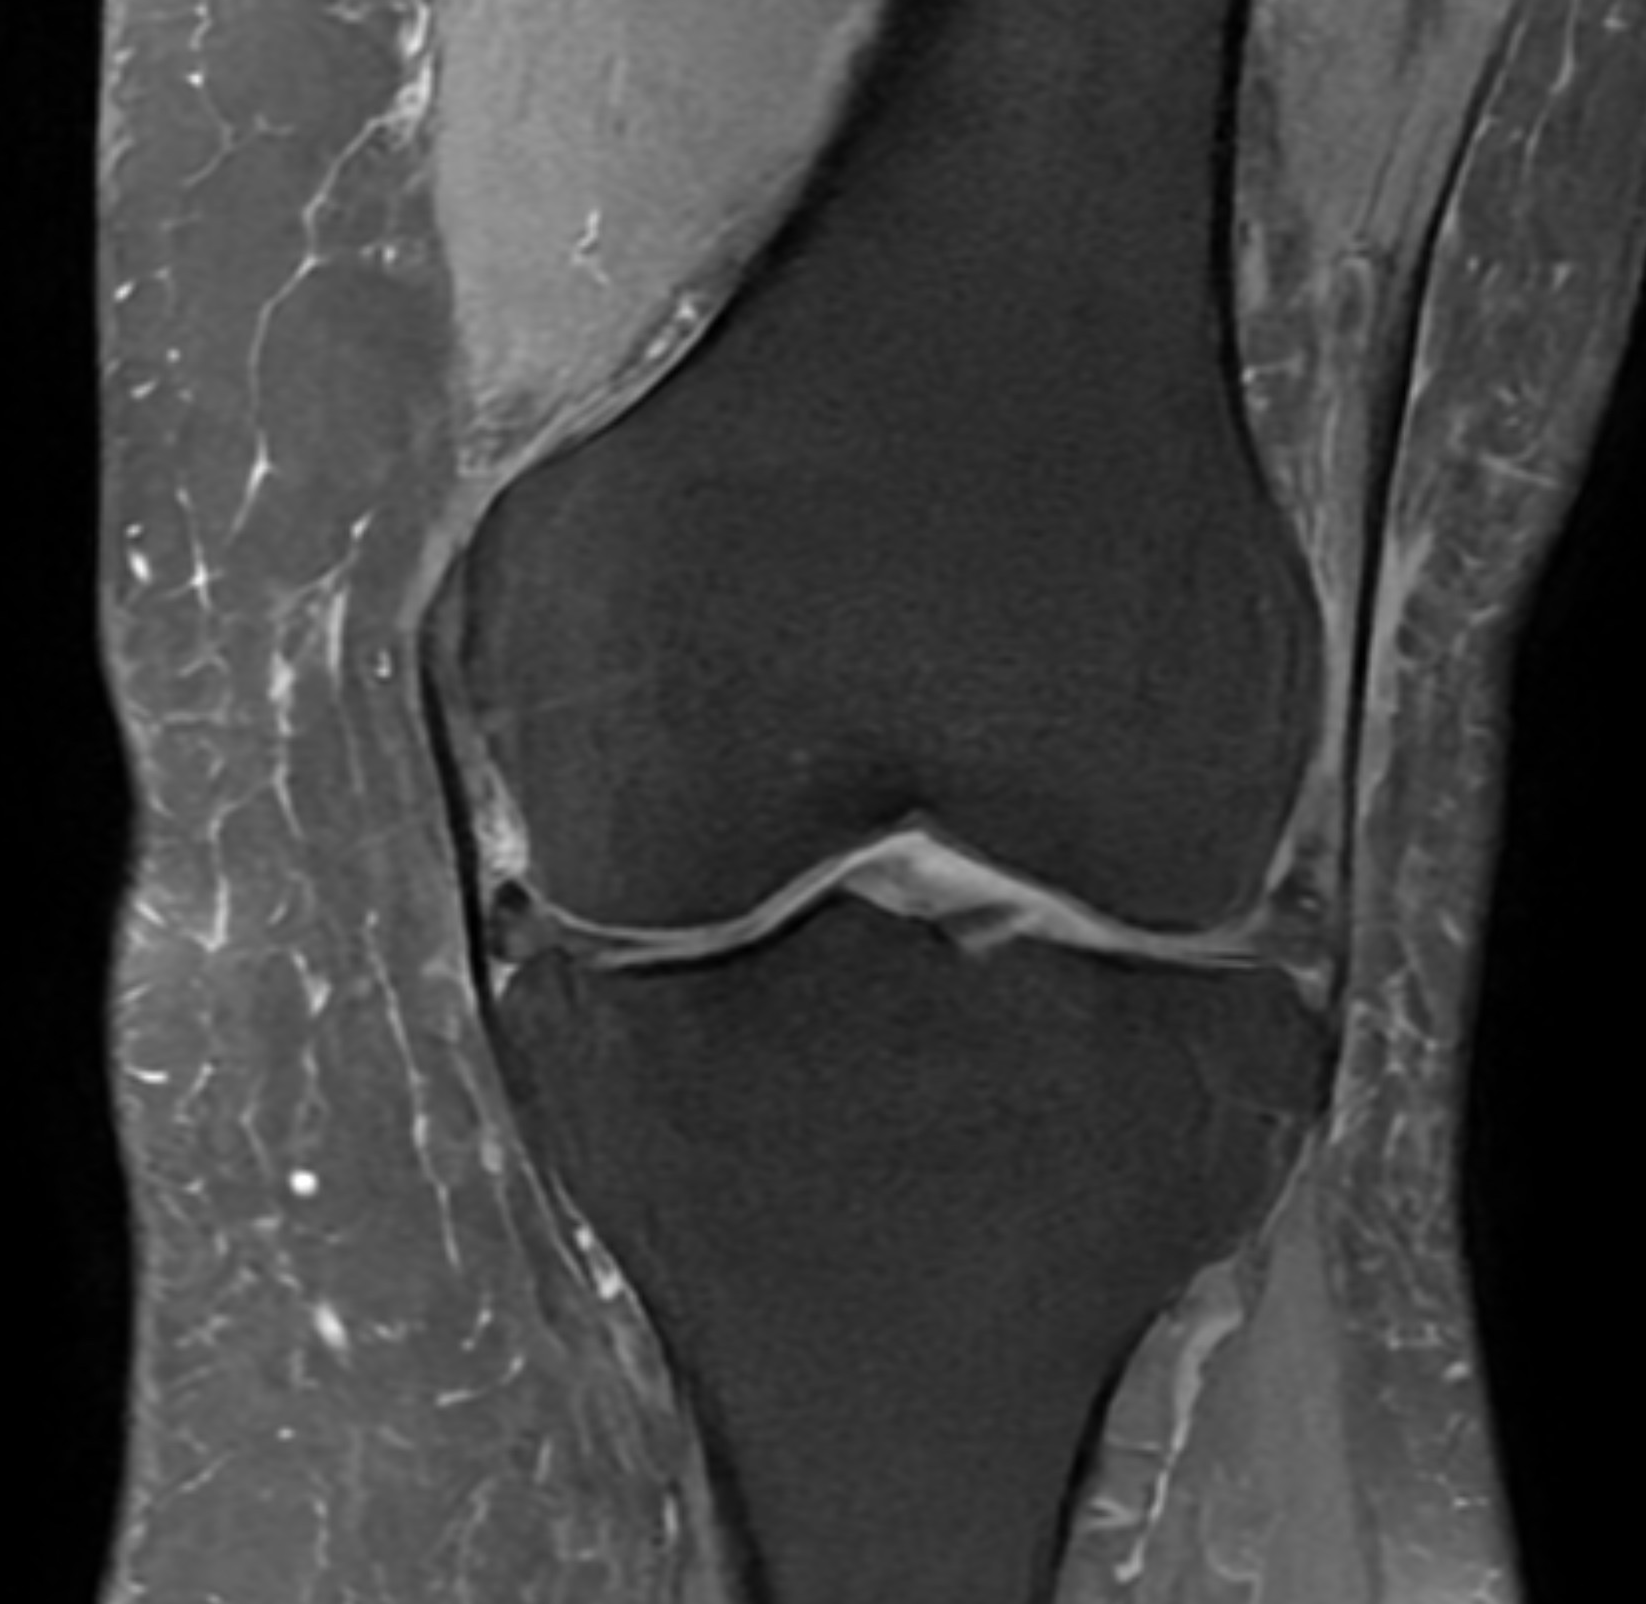

Magnetkameraundersökning (MR) är en avancerad bilddiagnostisk metod som ger detaljerade bilder av knäledens mjukdelar, såsom menisker, korsband, brosk och muskler. Till skillnad från röntgen kan MR visa skador som inte syns på traditionella bilder.

Undersökningen är helt strålningsfri och används ofta när man behöver en mer exakt diagnos.

Exempel på MR-fynd

Vid en MR-undersökning kan man ibland se flera samtidiga förändringar i knät. Ett exempel är degenerativa meniskskador, där vävnaden har förändrats över tid och kan ha sprickor (rupturer).

I vissa fall ses även:

- Bevarat eller lätt påverkat ledbrosk

- Diskreta förändringar i korsband utan total ruptur

- Ökad mängd ledvätska (tecken på irritation)

- Mindre cystor, exempelvis Bakercysta

Dessa fynd behöver alltid tolkas i relation till symtom för att avgöra betydelsen och eventuell behandling.